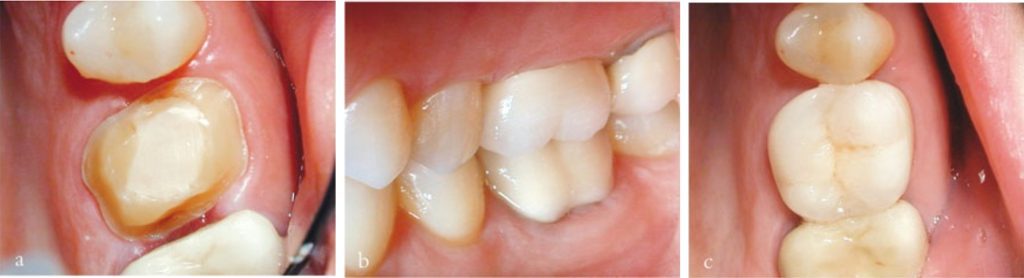

Thông thường, răng cần điều trị nội nha thường đã được phục hồi lớn trước đó hoặc bị bể vỡ và nhiễm khuẩn.

Lý tưởng nhất là nên có tối thiểu 2 mm mô răng lành nằm trên nướu bao quanh toàn bộ chu vi răng để thuận lợi cho phục hồi sau đó.

Nếu có bất kỳ nghi ngờ nào về khả năng phục hồi răng (xem chương 8) thì cần tháo bỏ hoàn toàn phục hồi hiện có để xác định rõ mức độ và vị trí mô răng lành còn lại.

Việc loại bỏ hoàn toàn phục hồi hiện tại được khuyến cáo trong nhiều trường hợp, vì có thể làm lộ ra các đường nứt ẩn không được phát hiện qua khám lâm sàng bên ngoài hay thăm dò nha chu.